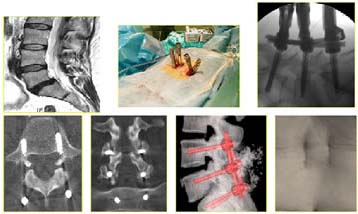

Es una combinación de cirugía mínimamente invasiva, endoscópica con cirugía de pequeñas incisiones, se colocan retractores tubulares y se insertan con un endoscopio.

La Cirugía Mini-Open ayuda a reducir el riesgo de infección y disminuye notablemente el dolor post operatorio y facilita una recuperación más rápida, sin dañar los músculos, en cambio la Cirugía abierta tradicional requiere de una incisión grande y se corta a través de los músculos. Los endoscopios son tubos delgados, acoplados con una fuente de luz y una cámara que permite al cirujano visualizar la cirugía en un monitor.

Permite Cirugías ambulatoria, la pérdida de sangre se reduce así como el tiempo de hospitalización. Los pacientes regresan al trabajo mucho antes.

Es de utilidad:

- Hernias Discales, Cervicales y Lumbares.

- En Raquiestenosis (conducto estrecho).

- Espondilolistesis (desplazamiento de una vértebra sobre otra).